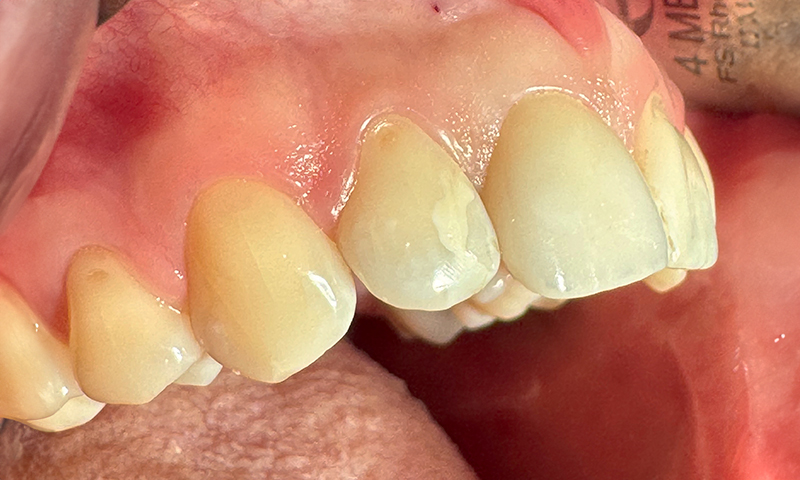

Fig. 15 (caso 3) - Quadro clinico occlusale 5 anni dopo l'impianto. Conservazione della cresta alveolare

Fig. 16 (caso 3) - Quadro clinico frontale 5 anni dopo l'impianto